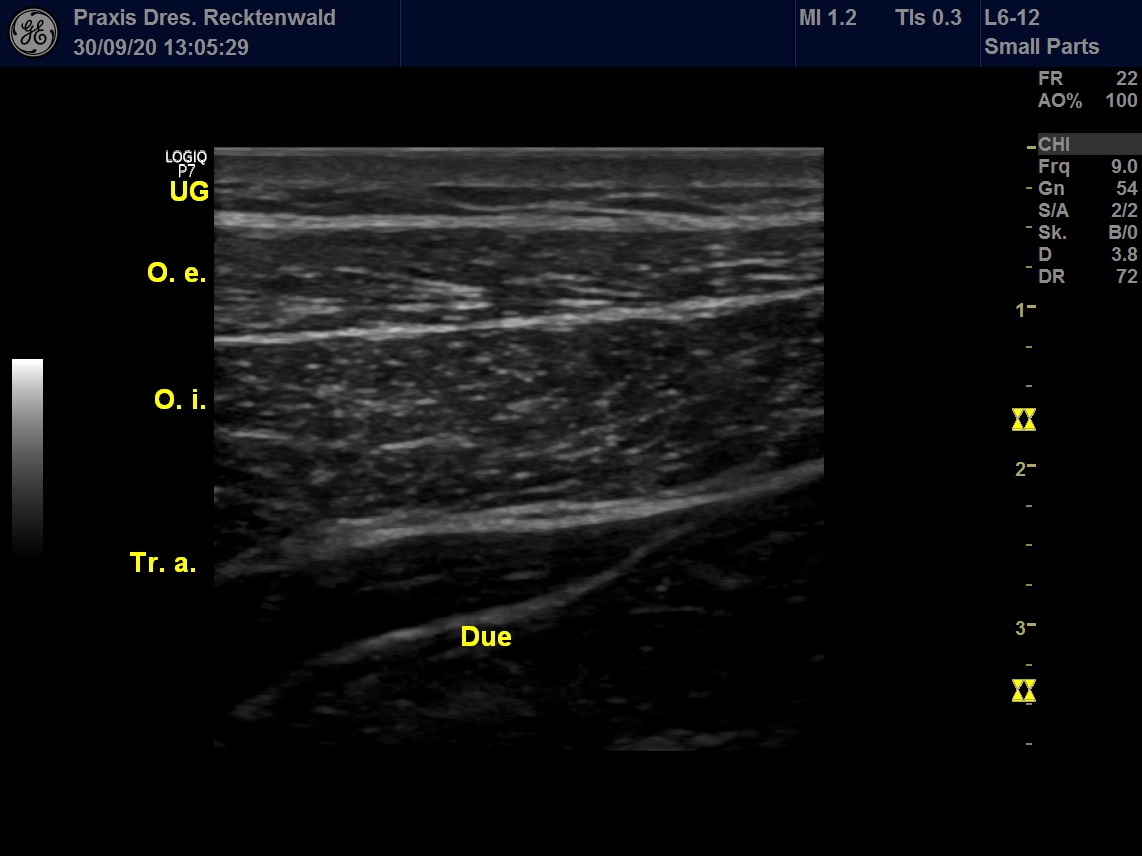

UG: Unterhautgewebe

O. e.: M. obliquus externus (oberer schräger Bauchmuskel)

O. i. : M. obliquus internus (tiefer schräger Bauchmuskel)

Tr. a.: M. transversus abdominis (tiefer querer Bauchmuskel)